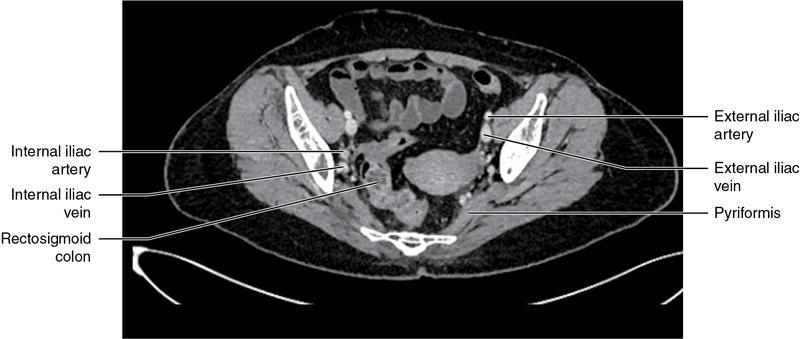

CROSS SECTIONAL ANATOMY OF ABDOMEN Satya Jha NORMAL ANATOMY OF ABDOMEN AND PELVIS Amandeep Singh The two major surfaces: The anterior and posterior layers of the coronary ligament converge on bare area (not covered by peritoneum). Its right and left margins form the right and left triangular ligaments. The right triangular ligament extends toward the diaphragm and separates right subphrenic space from right subhepatic space. The left triangular ligament gives tracts extending to the diaphragm and falciform ligament and does not compartmentalize the left subphrenic space. Ligamentum teres or the obliterated umblical vein is contained in falciform ligament which attaches the liver to anterior abdominal wall. The main portal vein, the proper hepatic artery and the common bile duct are contained within investing peritoneal folds of hepatoduodenal ligament at the porta hepatis (Fig. 7.2.2.1). Liver is divided into eight segments which are functionally independent and have their own vascular supply and biliary drainage. Arterial circulation: The branches of the hepatic artery accompanying the portal veins. Hepatic venous system: The right, middle, and left hepatic veins draining into IVC (Figs. 7.2.2.2 and 7.2.2.3). The gallbladder is a blind pear-shaped muscular membranous sac which is an embryologic derivative of the foregut, is a pouch lying along the undersurface of the liver. The gallbladder fossa is located in the plane of the interlobar fissure, which lies between the right and left hepatic lobes. Its major function is to store and concentrate bile which is produced by the liver. It measures approximately 4 cm in diameter when it is normally distended. Gallbladder is a smaller tubular structure in contracted state. The normal gallbladder wall thickness ranges from 1 to 3 mm. The gallbladder is divided into the fundus, body and neck. Infundibulum is present in the region of neck of the gallbladder, which is called the Hartmann pouch, where gallstones are usually impacted. Intrahepatic biliary radicles (IHBRs) scattered throughout the liver get confluent towards the hilum. They unite to form the right and left main hepatic ducts which further unite to form common hepatic duct (CHD) at the hilum. Common bile duct is formed by the union of cystic duct with common hepatic duct. The main pancreatic duct is joined with the common bile duct to form the ampulla of Vater at the major duodenal papilla (Figs. 7.2.2.4 and 7.2.2.5). Pancreas is located in anterior pararenal space of retroperitoneum anterior to perirenal (Gerota’s) fascia and posterior to parietal peritoneum. It is divided into head, uncinate process, neck, body and tail from right to left. Pancreas lies anterior to portal vein, which marks the point of transition between the body and neck. The region between head of pancreas and second and third parts of duodenum is known as the pancreatic groove. In postnephrectomy cases or with agenesis of kidney or ectopic kidney, pancreas moves posteriorly to partially fill in the empty renal fossa; its soft tissue density should not be mistaken for recurrent tumour. It is located in the pancreatic groove and is bounded superiorly by the duodenal bulb, laterally by second portion of duodenum, inferiorly by third portion of duodenum, medially by superior mesenteric vein and anterior to inferior vena cava. It is a wedge or wedge shaped lying posterior to superior mesenteric artery and vein. It is an imaginary junction between the head and body and lies directly over the junction of the splenic vein and superior mesenteric vein. It is located posterior to the lesser sac and anterior to the aorta, left adrenal gland, left kidney, and renal vessels and runs obliquely upward to the left of the superior mesenteric vessels. It is situated median to the colonic flexure and anterior to the left kidney. It is located in close proximity to the splenic hilum without a notable relation with the body of pancreas. It is seen anterior to the left kidney and median to the colonic flexure. The distal part of the tail passes between the peritoneal layers of the splenorenal ligament (Fig. 7.2.2.6 and 7.2.2.7).